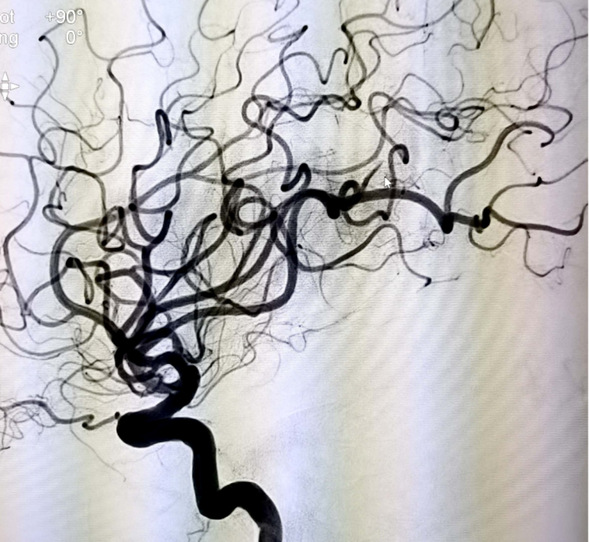

术后颈内动脉侧位造影

当天15点47分,一位老年男性患者在家中看电视时突发右侧肢体活动不灵,不能言语,家属紧急将其送往我院急诊就诊并联系神经内五科迟景宏主任。16点40分,患者在家属陪同下来到我院急诊。迟景宏主任在紧急查看患者病情并完善相关检查后,果断判断患者为急性大血管闭塞,通过与患者家属交代病情,征得了患者家属的同意,决定对其行静脉溶栓治疗。经验丰富的迟景宏主任判断单一溶栓难以缓解患者大血管闭塞所导致等症状,立即请介入放射科刘琳主任、莫庆国副主任进行会诊,建议桥接取栓。17点25分,患者顺利完成主动脉弓上脑血管造影证实左侧大脑中动脉下干闭塞。根据患者病情,神经、介入团队经商议后决定行BADDASS治疗,三件套组合:BGC+中间导管+长取栓支架,交换8F动脉鞘,引入BGC:8F×95cm;颅内支持导管:5F*125cm;取栓支架:4mm*20mm至远端病变血管,透视下释放取栓支架至病变血栓处,停留8分钟后取出大量血栓,一次取栓成功,达到三级再通。复查造影见左侧颈内动脉、左侧大脑前动脉、左侧大脑中动脉显影正常,血流改善,各分支显影良好,M1段未见明显狭窄,术中复查C臂CT未见颅内出血。19点10分,手术顺利结束,术后患者意识清楚,肢体活动较前明显改善,后经对症及康复治疗,患者于2月1日顺利出院,出院时患者恢复如常。通过医生的准确判断、过硬的医疗技术、团队的紧密配合,患者从入院到成功救治在150分钟内顺利完成。